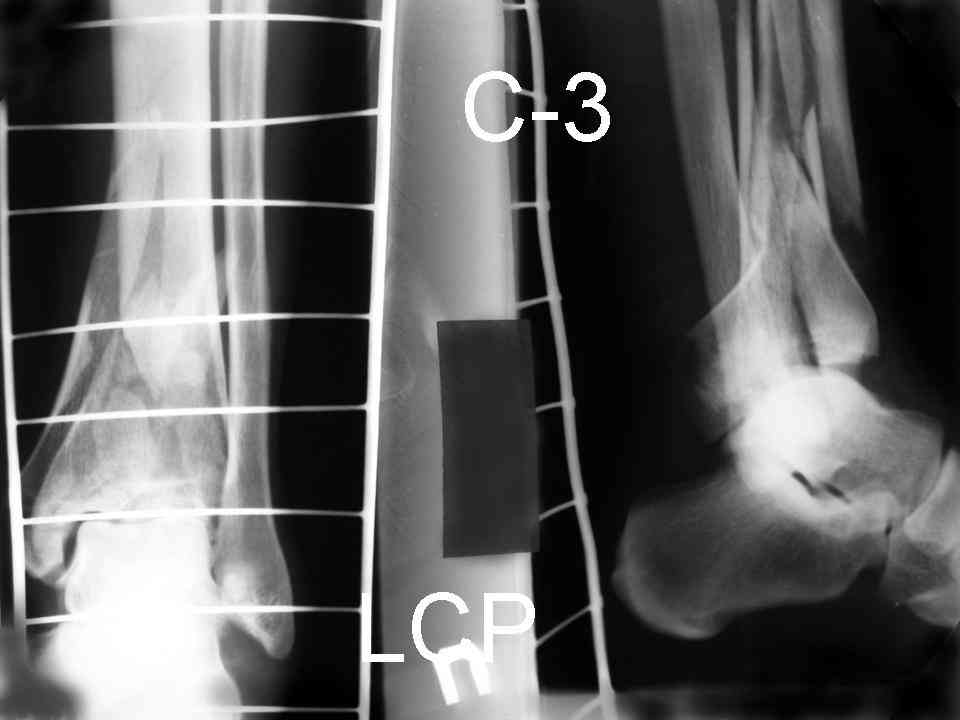

Это типичный перелом пилона, который надп лечить только открыто.Извини те что опоздал к обсуждению, но даже если вы уже оперировали больного по Илизарову это даже лучше.Посылаю картинки.

Посмотрим вроде прошло если понравится напишите расскажу как это сделать.По принципам АО кстати при поступлении сначала восстанавливают длину малоберцовой кости фиксируют пластиной 1/3 трубки потом накладывают аппарат наружной фиксации и через 7-10 дней открыто восстанавливают большеберцовую кость.С уважением Дрягин

На рентгенограммах типичный перелом пилона по типу С-3. есть опыт до 100 открытых опреаций у нас в клинике. 20 примерно в год. Принцип один -все внутрисуставные переломы нуждаются в открытой репозиции и внутренней стабильной фиксации. При поступлении КТ не надо, так как получается только нагромождение костей. Истинной картины нет. Главное восстановить длину малоберцовой кости - это ключ к успеху. При поступлении меньше всего надо думать о сосудистых расстройствах, т.к. сама операция и репозиция даже сначала частичная даёт улучшение сосудитых нарушений. Причём очень быстро. Операция в 2этапа. При поступлении доступ позади наружной лодыжки, причём обязательно. После этого репозиция малоберцовой кости и фиксация пластиной 1/3 трубки под винт 3,5. Дренаж и любой аппарат наружной фиксации. Затем после спадения отёка на 5-7-10 день аппрат снимается и дугообразный разрез спереди от медиальной лодыжки 10-12 см. Главной чтобы расстояние между 1 и вторым разрезом было не меньше 7-8 см. Тогда не будет некрозов лоскутов. Таранная кость используется как матрица на неё укладываются отломки и фиксируются пицами. Ренг-контроль. Отломки лежат все отдельно, но ничего не высыпется. При переломах С-3 всегда нужна костная пластика (из крыла). Фиксация пластиной лист клевера простой или LCP. Гипс не нужен. Дренаж до 48 часов. Операция длится 3-4 часа обязательно без жгута. Посылаю примерно такой же случай.

Послала ещё два снимка, если не пройдут, пошлю ещё. Дрягин. Если есть вопросы, готов ответить.